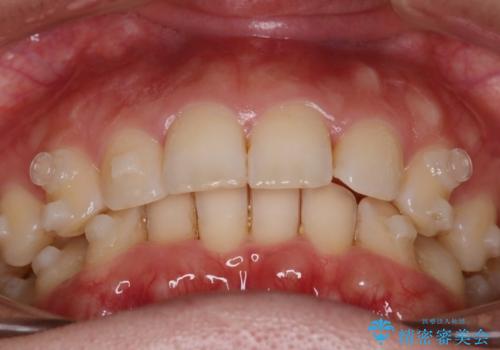

- 下の歯のがたつきを主訴に来院されました。

下の歯のがたつきと右の奥歯の噛みあわせ改善するために治療計画を立てることにしました。

右側臼歯部の咬合改善のために、臼歯部のみ部分的なワイヤー矯正を行い、咬合改善がみられてからインビザラインにて全体的な矯正を行なっていく治療計画を立てました。